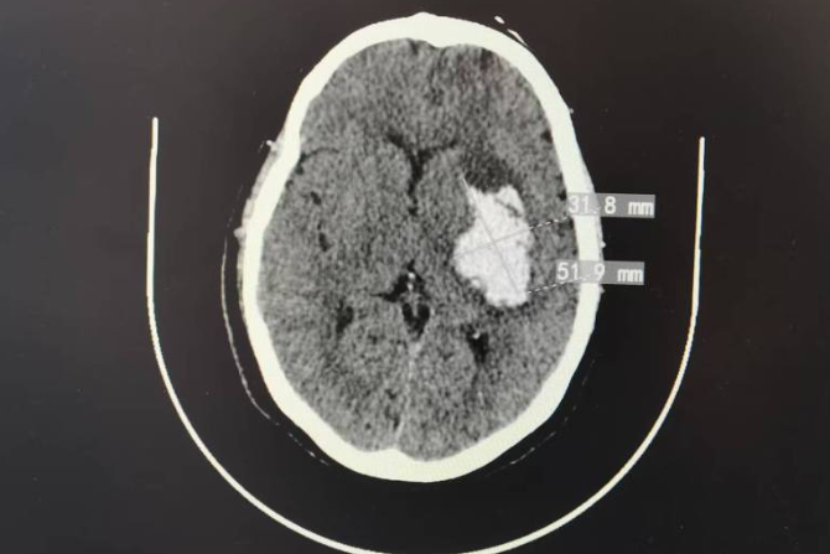

高血压脑出血被称为中老年人的‘隐形炸弹’,一旦破裂,急性期致死率可达30%-50%,致残率高达50%-70%,是严重威胁生命健康的急危重症。近日,日照市康复医院神经康复科上演了一场惊心动魄的“生命保卫...